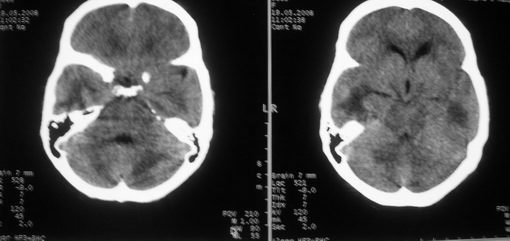

以下是引用zjzjr在2008-5-19 13:40:00的发言:[br]支持左上肺周围型肺癌(腺癌可能性大)伴颅内多发性转移.